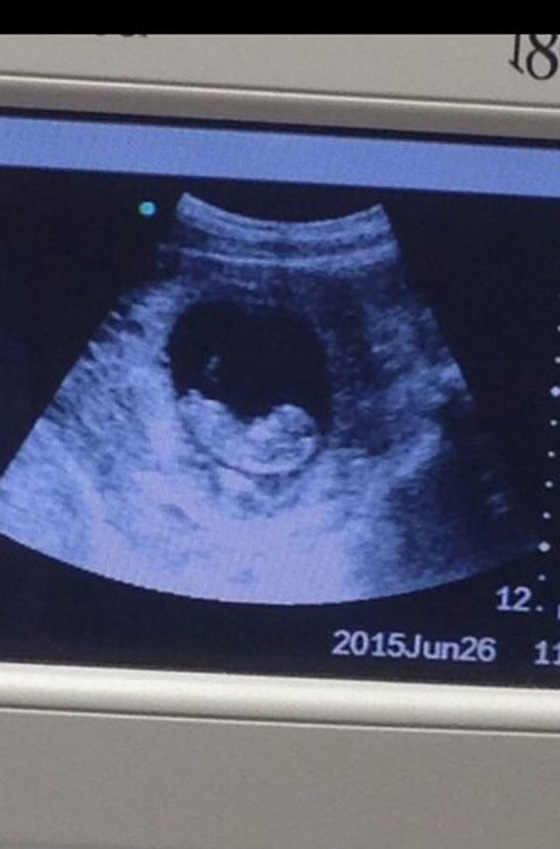

تظهر صورة في البداية وكأنها صورة تذيب القلوب لطفل لم يولد بعد يستريح بهدوء في رحم والدته، لكن عند تدقيق النظر يظهر شئ تقشعر له الأبدان. ذهبت صورة كالفيروس على الإنترنت لكائن غريب بجوار جنين بعد تسجيل لقطات له خلال فحص بالموجات فوق الصوتية. حققت الصورة أكثر من 979 ألف مشاهده منذ تحميلها أمس على الموقع، حيث انقسم مستخدمو مواقع التواصل الإجتماعى في تحديد ماهية هذا الكائن الغريب، فجاءت أغلب التعليقات بين إنه إله هندوسى، وحورية بحر، وشيطان. لم تكن هذه المرة الأولى التي يظهر فيها أشكال غريبة بجانب الأجنة، فقد ظهر من قبل شكل جد متوفى يقبل جنين بعد إجراء مسح4D.